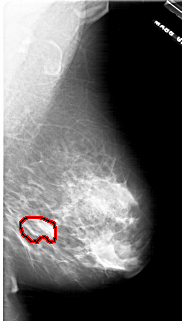

A_1771_1.RIGHT_MLO

RIGHT_MLO LINES 6091 PIXELS_PER_LINE 3451 BITS_PER_PIXEL 12 RESOLUTION 43.5 OVERLAY

FILE: A_1771_1.RIGHT_MLO.OVERLAY

TOTAL_ABNORMALITIES 1

ABNORMALITY 1

LESION_TYPE MASS SHAPE LOBULATED MARGINS ILL_DEFINED

ASSESSMENT 4

SUBTLETY 3

PATHOLOGY BENIGN

TOTAL_OUTLINES 1

BOUNDARY